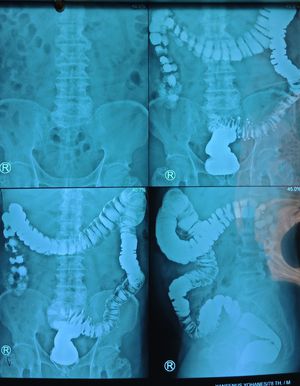

whats your diagnosis?

the patient came to outpatient clinic with the history long history of diarrhea, without fever, bloating and abdominal cramp.

barium enema showing abnormal splenic flexure 4th radiograph

Sigmoid diverticulosis